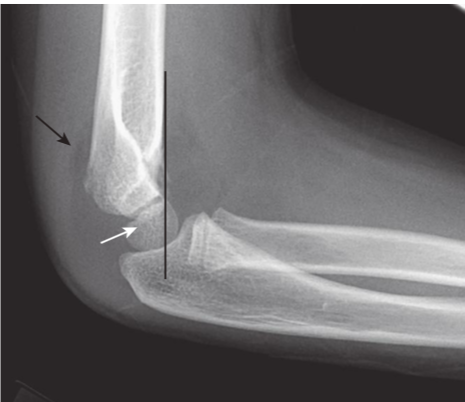

Supracondylar fracture.

A supracondylar fracture of the distal humerus is a common fracture in children, and its findings may be subtle. Most of these fractures produce posterior displacement of the capitellum of the distal humerus. On a true lateral film, the anterior humeral line (a line drawn tangential to the anterior humeral cortex and shown here in black) should bisect the middle portion of the capitellum (white arrow). When there is a supracondylar fracture, this line will pass more anteriorly, as it does here. There is a positive posterior fat pad sign present (black arrow).